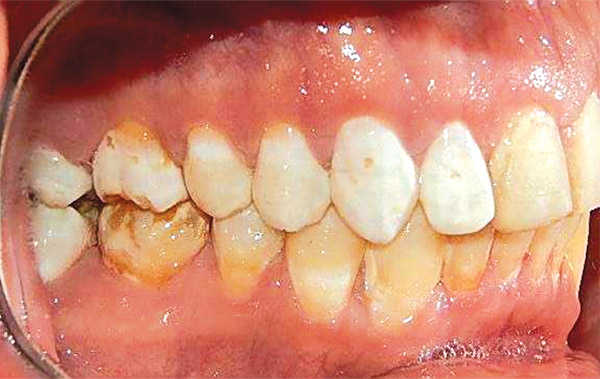

En las fotografías intraorales se muestra la fluorosis dental Tf4 y Tf7, las relaciones molares clase II molar y canina bilateral (Figura 3 y 4), el apiñamiento severo superior e inferior, con el órgano dental 35 en infraoclusión. El overbite aumentado y las líneas medias dentales no son coincidentes (Figura 5), las formas de arco superior e inferior son cuadradas (Figura 6 y 7).

Figura 3. Intraoral derecha.

Figura 4. Izquierda.